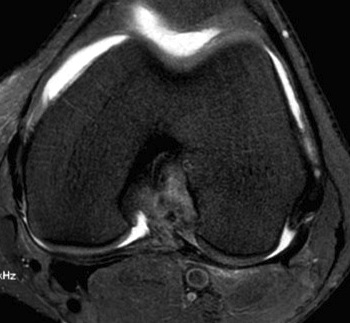

Axial MRI demonstrating no ACL attachment to lateral femoral condyle